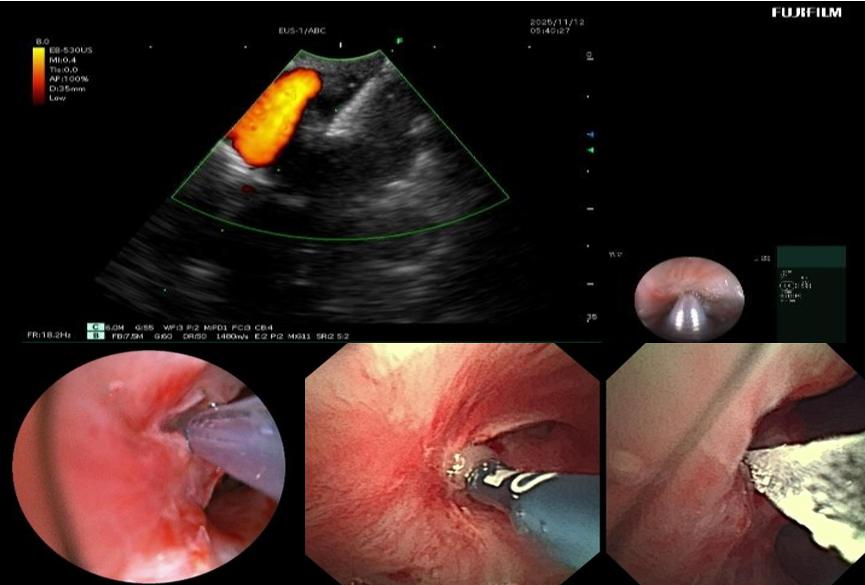

▲支气管镜下多种内镜器械联合使用

入院后,呼吸与危重症医学科介入团队对患者病情进行全面评估。完善胸部增强CT提示:右肺上叶大片状实变并坏死,支气管完全闭塞。由于前期单纯口服抗真菌药物效果不佳,因此联合气管镜下介入治疗势在必行。经过认真评判,团队制定了详细的气管镜下介入诊疗计划。治疗过程包括:超声支气管镜引导下精准穿刺,高频电刀微创开窗建立引流通道;钳夹清除远端大量坏死组织;局部灌注抗真菌药物以提高病灶药物浓度;结合球囊扩张与超细冷冻冻融治疗,扩大引流窗口;并多次行镜下冲洗,彻底清除分泌物与坏死物。

经过系统治疗,患者低热症状消失,精神状态逐步好转。术后气管镜复查显示右上叶前段闭塞支气管已重新开放,坏死物基本清除;胸部CT显示原新发病灶消失,前段病灶引流通畅,炎症吸收良好,成功保留了右肺功能。